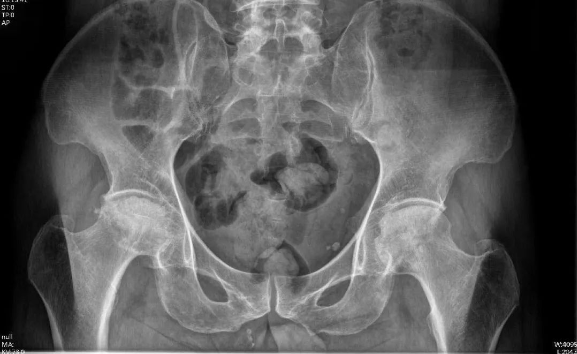

入院后,通过完善X线片、三维CT、MR等相关检查。发现周先生双侧股骨头坏死,尤其右侧股骨头严重变形,相关检查结果提示周先生的股骨头坏死已非常严重,双侧均达到Ficat分期Ⅳ期,右下肢较对侧缩短2cm。双侧髋关节旋转活动受限,右侧髋关节活动受限较重,双侧“4”字试验(+)。

术前DR